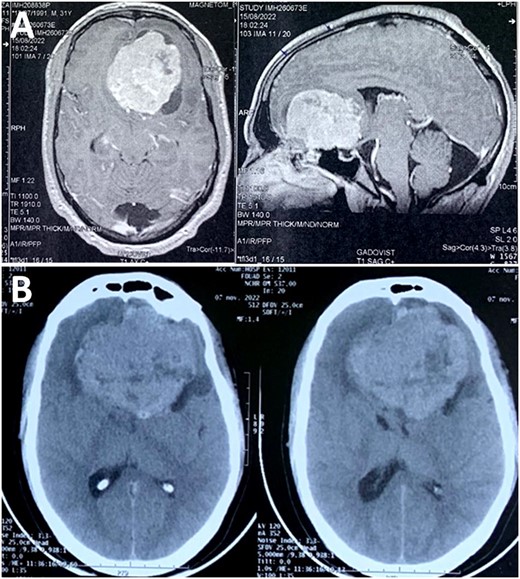

Magnetic resonance imaging (MRI) scan showed a skull base tumor that was hypointense on T1, hyperintense on T2, with regular and homogeneous contrast enhancement. The radiologist suggested an anterior skull base meningioma, although atypical for the age of the patient (Fig. 1). A control computed tomography (CT) scan—performed before admission—demonstrated a rapid growth of the tumor, almost reaching double the initial volume over a 2-month period, with perilesional edema (Fig. 1). This was clearly in favor of an aggressive behavior and questioning the suggested diagnosis of meningioma.

(A) MRI scan showing a skull base tumor that was hypointense on T1, and hyperintense on T2, with regular and homogeneous contrast enhancement; (B) CT scan demonstrated a rapid growth of the tumor, almost reaching double the initial volume over a 2-month period.